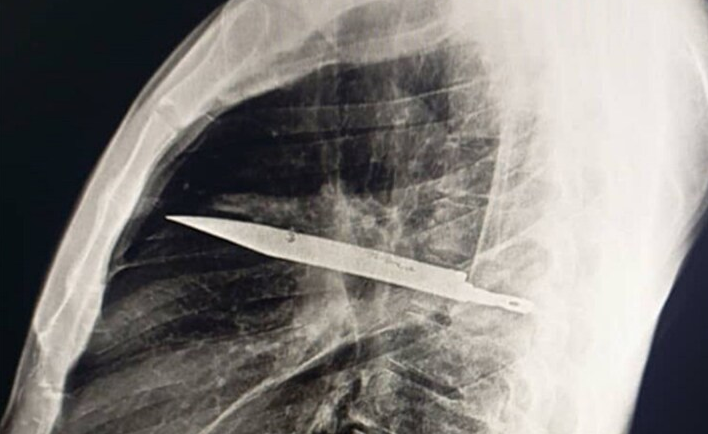

ونشر أطباء مستشفى موهيمبيلي الوطني في تنزانيا مؤخرًا دراسة حالة غير عادية في مجلتهم العلمية "المكتبة الوطنية للطب". وشرحوا حالة رجل يبلغ من العمر 44 عامًا يتمتع بصحة جيدة بشكل عام جاء إلى المستشفى بتاريخ طويل من إفرازات صديدية بيضاء من حلمة ثديه الأيمن. وقال التقرير أن المريض أنكر أي ألم في الصدر أو صعوبة في التنفس أو سعال أو حمى، لكنه سُئل عما إذا كان لديه أي شيء جدير بالذكر ليخبر الأطباء، فتذكر مشاجرة عنيفة قبل ثماني سنوات، أصيب خلالها بعدة جروح في وجهه وظهره وصدره وبطنه، حيث تمكن الأطباء من خياطة الجروح آنذاك، وعاش حياة هادئة في الغالب منذ ذلك الحين، حتى بدأت حلمة ثديه تفرز صديدًا. ولم يتمكن الأطباء من تحديد السبب، فأمروا بإجراء فحص بالأشعة السينية، ليصدموا برؤية نصل سكين ضخم عالق في صدر الرجل. وكتب الأطباء في دراسة الحالة: "أظهر التصوير الأولي بالأشعة السينية الجانبية للصدر وجود جسم معدني عالق في منتصف الصدر، مع وجود تعتيم محيط به، يُحتمل أن يُمثل ورمًا دمويًا موضعيًا مزمنًا أو تليفًا ما بعد الصدمة، وهو أحد مضاعفات طعنة المريض".

وبطريقة ما، تمكنت نصل السكين، الذي دخل من خلال لوح الكتف الأيمن، بأعجوبة من تفادي أي أعضاء رئيسية. في وقت مشادة الرجل، قبل ثماني سنوات، لم يكن لدى المستشفى الذي عولج فيه أي وسيلة لإجراء فحص إشعاعي، ولأنه لم يُبلغ عن أي ألم بعد شفاء جروحه، لم يُكلف أحد نفسه عناء إجراء المزيد من التحقيقات. والأغرب من ذلك أن السكين لم يُسبب للمريض البالغ من العمر 44 عامًا أي إزعاج لفترة طويلة. لكن القيح كان ناتجًا عن تراكم الأنسجة الميتة حول الجسم الغريب. وبعد هذا الاكتشاف المروع، تم استخراج السكين بعناية أثناء الجراحة مع الأنسجة الميتة والقيح. وأمضى المريض 24 ساعة في وحدة العناية المركزة قبل نقله إلى الجناح العام لعشرة أيام أخرى. وسارت عملية تعافيه على ما يرام، وكانت المتابعات اللاحقة خالية من أي مشاكل.